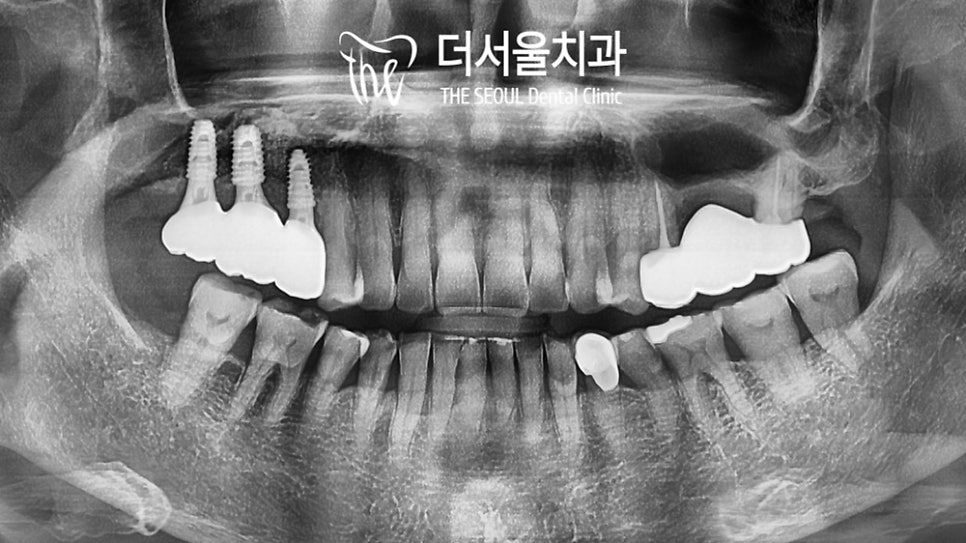

심은 곳이 모두 다 안정적으로

골 유착이 이루어진 것을 확인한 뒤에는

곧바로 최종 보철 결합을 도와드려야겠죠?

그래야 임플란트 축농증 이 생기지 않고

건강하게 오래 사용할 수 있기 때문이죠^^

성남치과에서 반대쪽 어금니는

브릿지 제작을 통해 개선을 도와드렸는데요.

양쪽 균형이 잘 맞을 수 있도록

교합 조정까지 확실하게 마친 이후에

모든 과정을 끝낼 수 있었습니다!